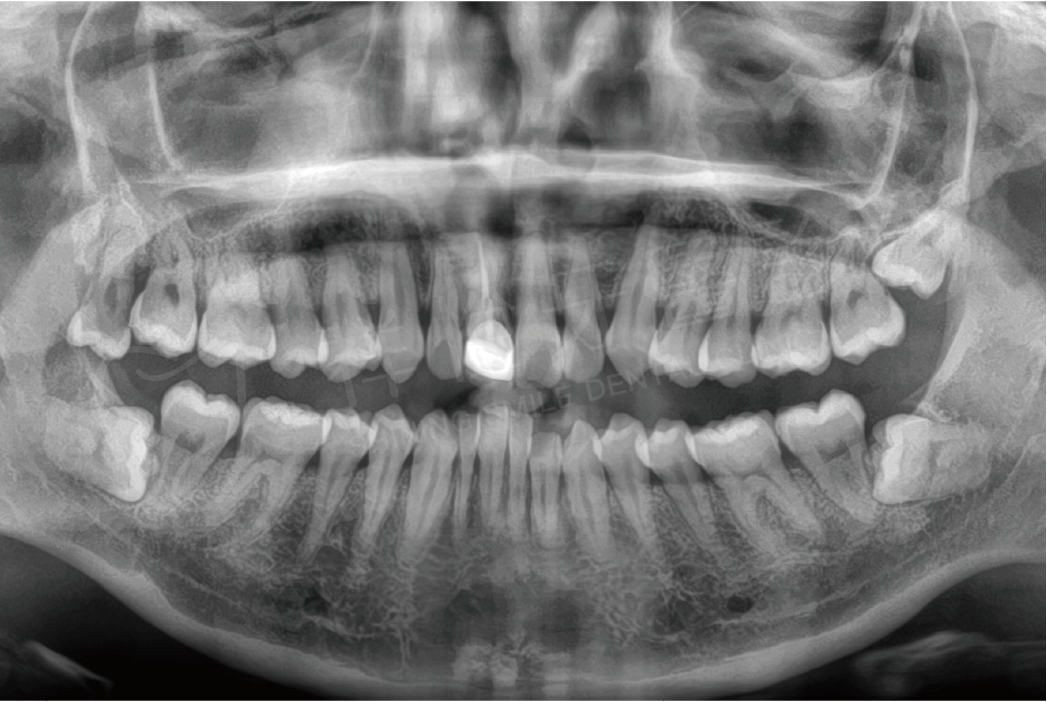

阻生齒拔除

拔牙前 拔牙後

拔牙前

拔牙後